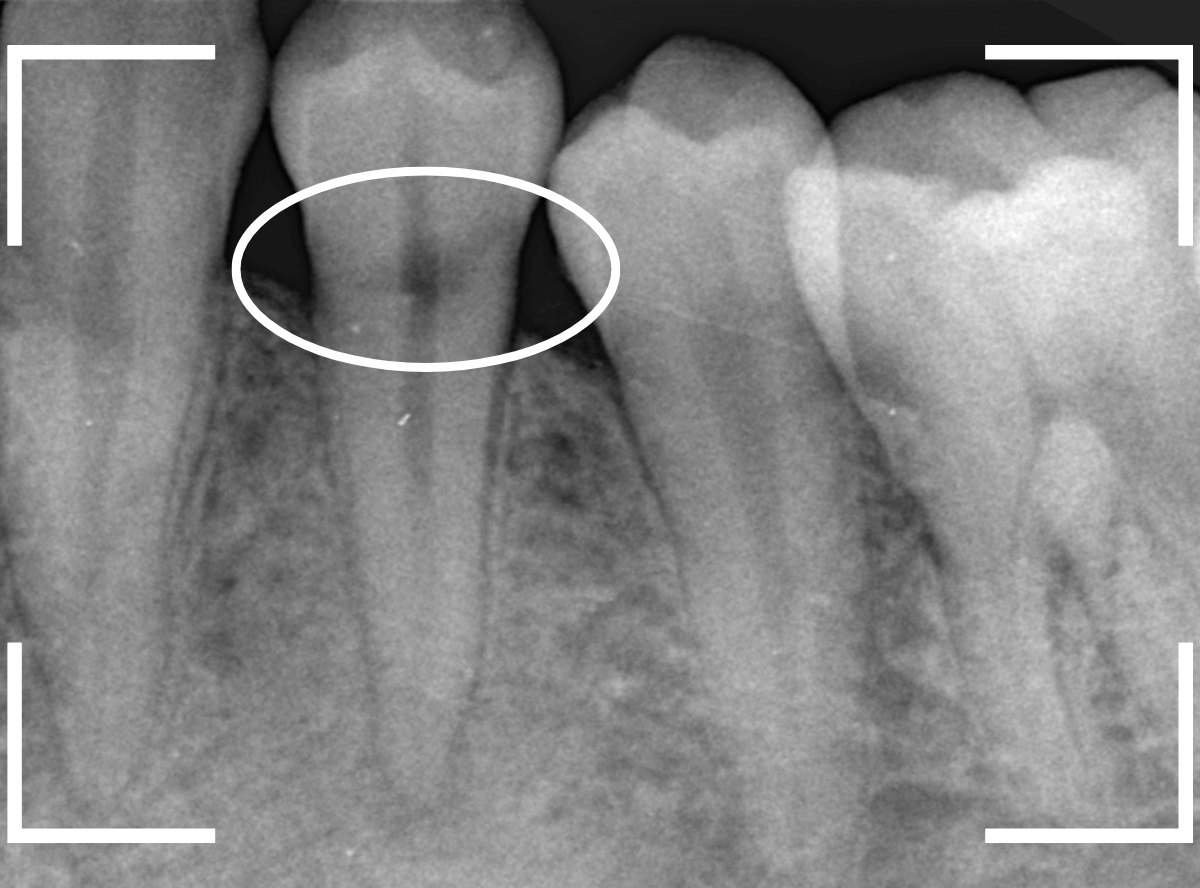

4. レントゲン写真での診断が難しい場合がある

虫歯の診断に非常に有効なレントゲン写真ですが、歯頚部う蝕に関しては限界があります。

レントゲン写真は2次元の画像です。

歯頚部う蝕は3次元的に進行するため、X線の照射方向によっては、う蝕が小さく見えたり、完全に隠れてしまったりすることがあります。

特に、唇側(唇に近い側)や舌側(舌に近い側)にできたう蝕は、進行がわかりづらい事が多いです。

レントゲン写真ももう一度確認してみます。

もしかすると、歯肉の中で虫歯が広がってるのかもしれません。

側面からの虫歯ですので、どれくらい虫歯が深いのかはこの写真からはわかりません。